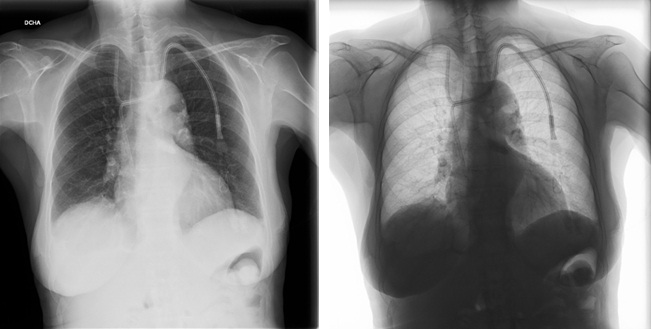

Semanas más tarde se detecta problemas de disfunción del catéter (altas presiones durante las sesiones de hemodiálisis en la rama arterial) que no mejoran con las maniobras habituales, se invierten las líneas con mejoría parcial y se utiliza uroquinasa según protocolo del servicio con escaso éxito. Dada la persistencia de disfunción se realiza radiografía de tórax comprobándose la migración de la rama arterial del catéter venoso a vena yugular interna derecha. (Imágenes 2 y 3)

Imagen 2. Rayos X de tórax. Proyección anteroposterior convencional y en negativo, 45 días posterior a la colocación catéter tunelizado yugular izquierdo